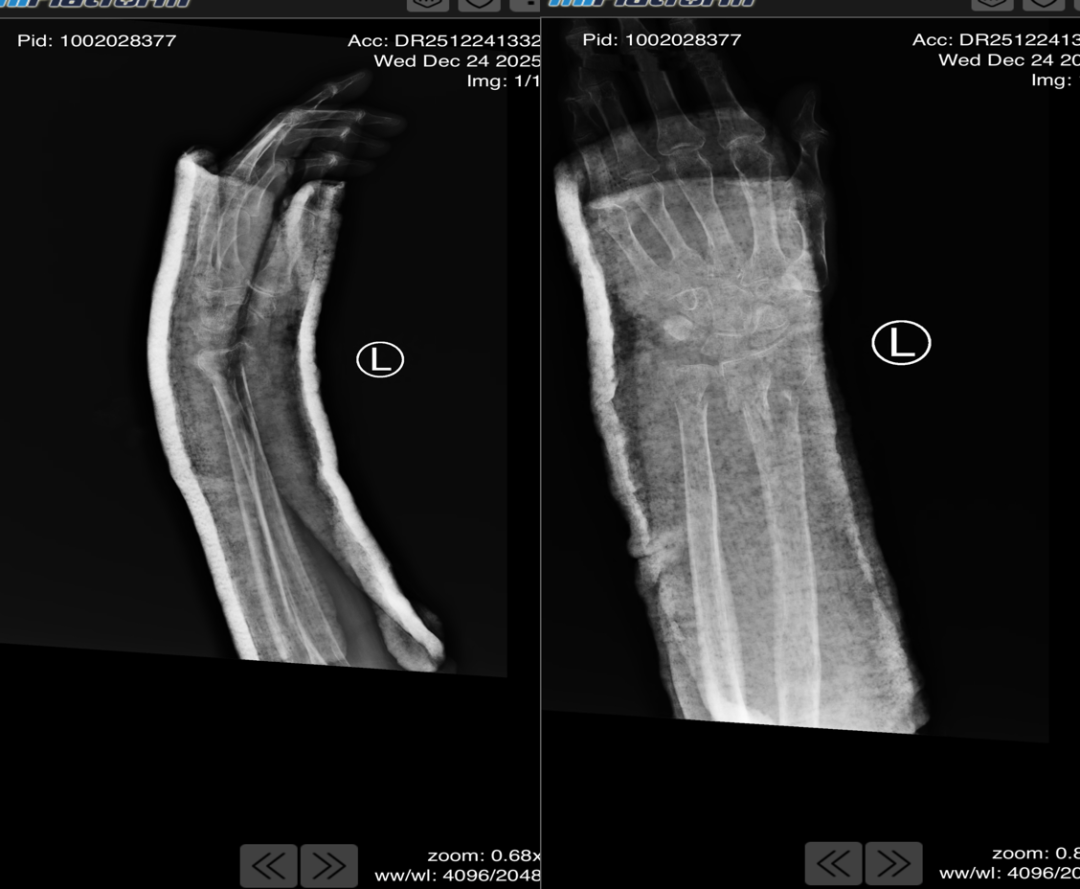

复位操作紧张有序展开:周健副主任医师稳握老人前臂反向牵引,把控力度与节奏,逐步拉开移位骨折端;董博主任专注腕部,对碎裂骨块精准实施折顶、旋转、推挤,手指灵活感知骨块位置变化;薛安邦医生密切观察老人面色、心率与反应,适时提醒调整力度,并用温和话语安抚分散其注意力。随着一声轻微的“咔嗒”骨擦音,移位的骨折碎块精准归位,老人呻吟声戛然而止,眉头舒展。 当董博主任宣布“复位成功”时,诊疗室里的众人都松了一口气,随即医护人员为患者进行石膏固定。复查X光片显示,骨折端对位对线良好,复位效果远超预期。

看着清晰的复查影像,家属紧紧握住医生的手,反复道谢。董博主任介绍,高龄粉碎性骨折的手法复位,既考验技术,更需耐心与责任心。西安市红会医院始终坚守以精湛技术为患者减轻痛苦。目前,张奶奶腕部疼痛已明显缓解,后续将在指导下开展康复训练,逐步恢复腕部功能。